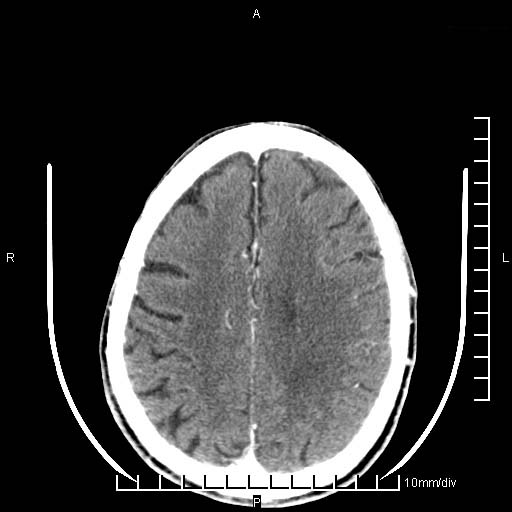

临床以双下肢浮肿,疼痛收治,无明显神经系统症状,既往无梗塞,出血病史。左颞叶见低密度灶,考虑什么?

无强化、 无占位、局部脑沟增宽, 软化灶吧。